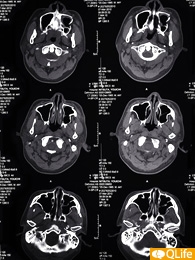

私は半月前にひどい頭痛がして、同時にめまいも起こりました。めまいの影響なのか、嘔吐も止まらなかったので、近くのクリニックを受診しました。そのクリニックにはMRIもあったので、ひどい頭痛と聞いたドクターはすぐにMRIを撮ってくれたのですが、画像では異常はないと言われました。ただ、検査の間も私が痛みを強く訴え、嘔吐を繰り返していたので、心配したドクターが入院治療の可能な病院を紹介してくれました。

紹介してもらった病院にはすぐに入院し、CT検査を受けました。しかし異常は見つからず、翌日には症状が治まったので退院しました。